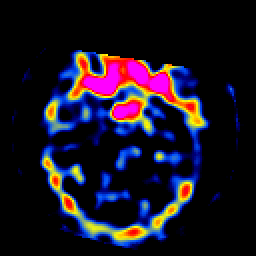

SPECT TL Study #8 -- Slice #17